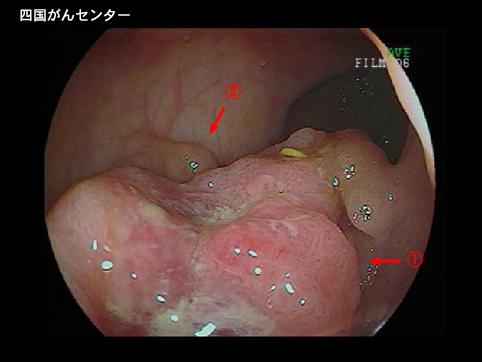

Posted by: Ehime Pref., National Hospital Organization Shikoku Cabcer Center

Criteria of Hist.ClassificationMalignant epithelial tumor/Others

LocationLarge intestine(Colon)/Rectum

Technique, MethodEndoscopy

Macroscopic TypesType 2 Ulcerated type with clear margin/

Size40 -

Depth of Tumor Invasionmuscularis propria